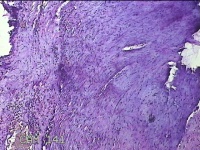

右侧卵巢囊肿

性别

女

年龄

36岁

临床诊断

一般病史

发现双侧附件囊肿1年。

标本名称

大体所见

灰白暗红色囊壁样组织2.5x2x0.3cm一块,表面光滑,部分已切开,囊内容物已流失,囊壁厚0.2cm。

考虑:子宫内膜异位囊肿。